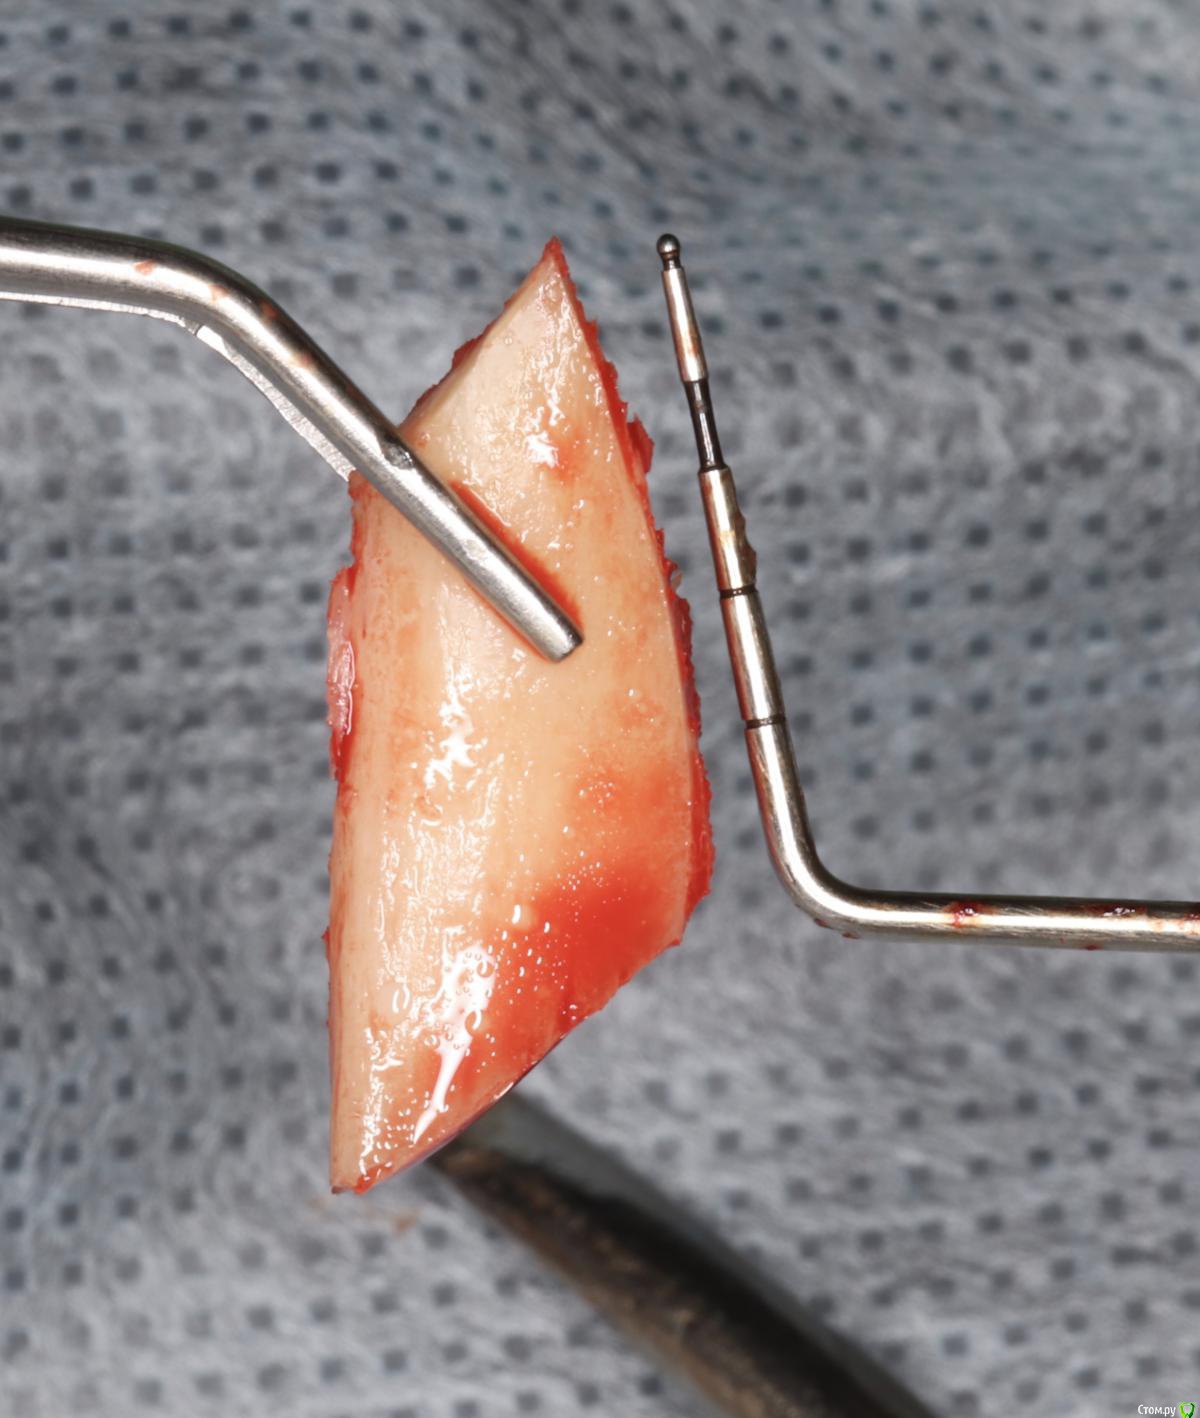

Doctor Vlad Опубликовано 27 августа, 2020 Поделиться Опубликовано 27 августа, 2020 а чем перекрывали аугментат? сопелька? Ссылка на комментарий

Александр07 Опубликовано 30 августа, 2020 Автор Поделиться Опубликовано 30 августа, 2020 а чем перекрывали аугментат? сопелька?Если имеете ввиду Прф то да Ссылка на комментарий

Doctor Vlad Опубликовано 31 августа, 2020 Поделиться Опубликовано 31 августа, 2020 Если имеете ввиду Прф то дада. я название забыл) Ссылка на комментарий